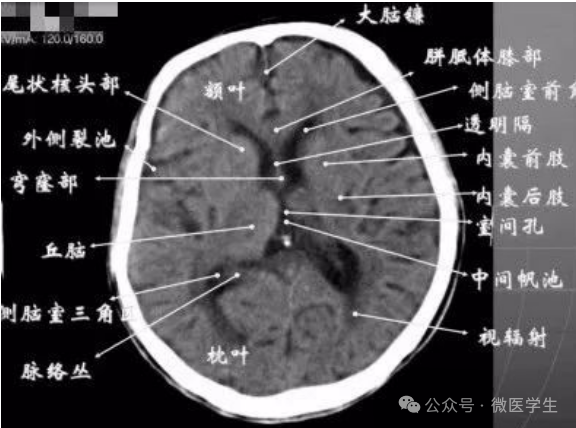

- 基底核、丘脑。

- 内囊前脚(前肢);尾状核和豆状核之间。

- 内囊膝部和后脚(后肢):位于豆状核(由外侧的壳核和内侧的苍白球组成)及丘脑之间。

- 壳核的外侧:外囊、屏状核、最外囊、岛叶(脑岛)。

- 四叠体池:两侧枕叶之间,池内有松果体,向前与第三脑室连接。

基底节(基底核):

- 埋藏在两侧大脑半球深部的灰质核团,是组成锥体外系的主要结构。

基底节区:概念不清。

可能包括:基底节、黑质、红核、及其周围白质区域。

- 内囊:位于丘脑、尾状核、豆状核之间的白质区,是由上、下行的传导束密集而成。分为三部分:前肢、膝部、后肢。膝部由皮质脑干束;后肢有皮质脊髓束、丘脑皮质束、听辐射和视辐射。

- 外囊:是位于屏状核和豆状核之间的白质带,主要由岛叶发出的皮质被盖纤维组成。

由额、颞、枕叶构成,两侧侧脑室体部之间为透明隔,外侧为尾状核和体部。侧脑室后角(枕角)可不对称,室内可见脉络丛钙化。中线处可见大脑纵裂池和大脑镰。